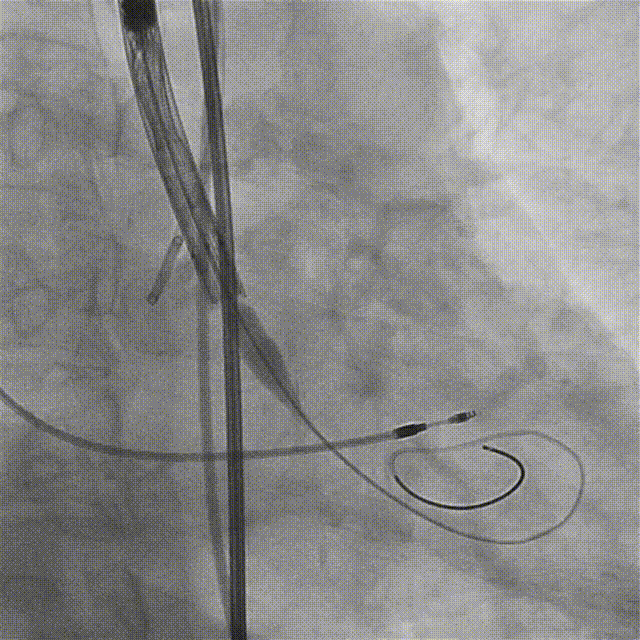

入路造影显示左髂总动脉-左股总动脉严重狭窄伴钙化

确认狭窄位置

送入v18导丝建立通路

送入6.5×60mm赛禾外周冲击波球囊

定位最狭窄处充盈至4atm进行脉冲治疗

脉冲释放一个周期(20秒)后,将冲击波球囊加压至6atm并保持球囊扩张30秒,造影显示腰征消失,血管顺应性被改善

复查造影显示左髂总动脉-股总动脉狭窄较前明显减轻,管腔直径预估达到输送大鞘的要求